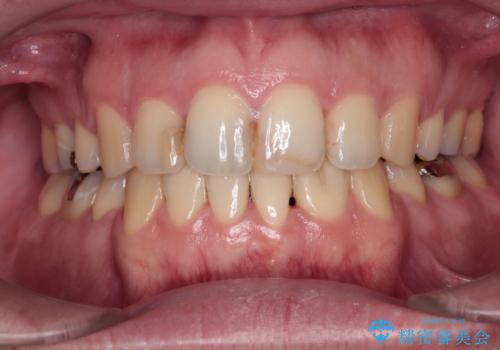

舌突出癖の改善トレーニングは、仕上がり、治療期間、そして治療後の後戻りに大きな影響を及ぼします。

トレーニングをしっかりと行っていただいたため、スッキリとした口元に仕上がりました。